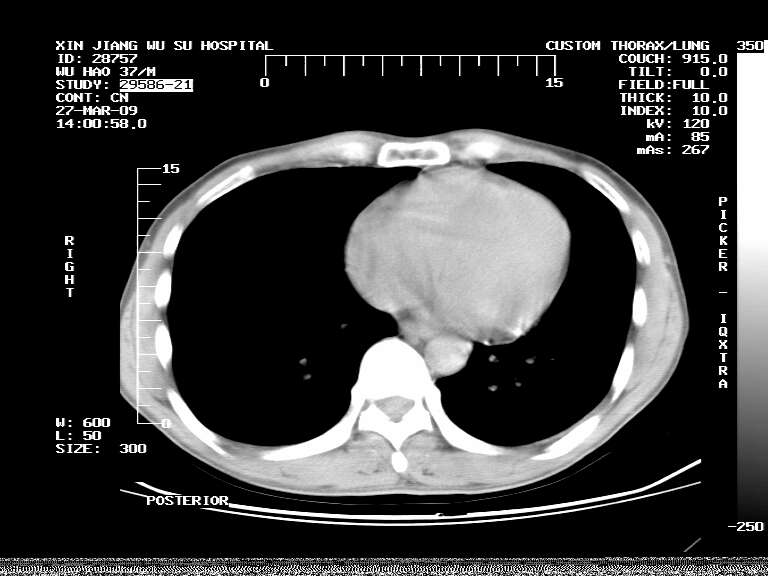

男,37岁,体检胸透发现阴影。

患者体检发现 无症状 左肺下叶占位,边缘模糊,可见血管聚束、分叶、胸膜牵拉,增强呈不均匀性强化。 首先考虑左肺下叶周围型肺癌,建议穿刺活检。

左肺下叶见一结节病变,边缘欠清不光滑,与胸膜粘连且胸膜局限性增厚,注药后呈环形强化,动脉期壁呈明显点环状强化,静脉期壁强化减低,中心密度低无强化,灶周无明显的卫星灶和水肿区(晕征)---考虑周围性肺癌,不除外感染性病变,建议穿刺活检。

左肺下叶软组织病灶,密度较高,内见点状钙化,其周围见子灶,邻近胸膜扁平样增厚.c+病灶强化明显,中心强化弱.诊断:左肺下叶结核瘤.

左肺下叶大片实变影,内靠胸膜见不规则更高密度结节灶,边缘强化,相邻胸膜增厚,胸膜下脂肪线存在。考虑炎症,结核可能。